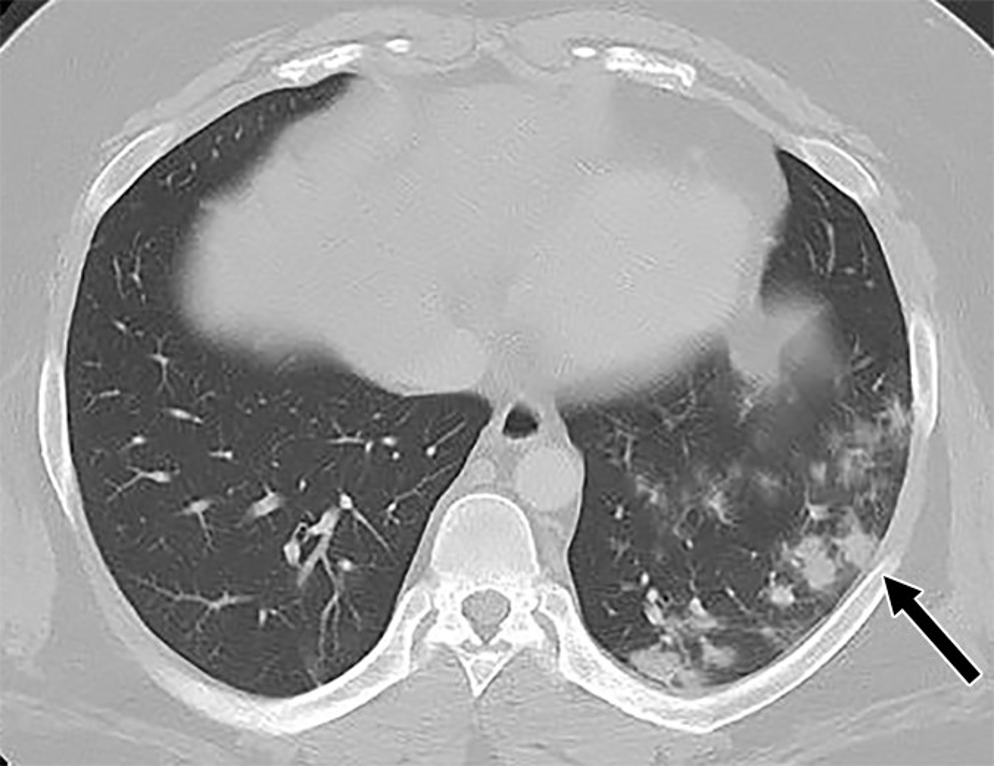

A computed tomography (CT) scan of the abdomen and pelvis revealed imaging findings in the lung bases of peripheral nodular airspace and ground-glass opacities. Abdominal imaging findings showed hepatosplenomegaly and severe hepatic steatosis; no abnormalities in the gastrointestinal tract, mesentery or vasculature; and no lymphadenopathy or ascites.

Subsequent CT chest and SARS-CoV-2 PCR testing confirmed the diagnosis of COVID-19. The patient was admitted to the hospital with a primary diagnosis of diabetic ketoacidosis, the likely cause of his abdominal pain, secondary to SARS-CoV-2 infection. The patient was discharged home 9 days later.